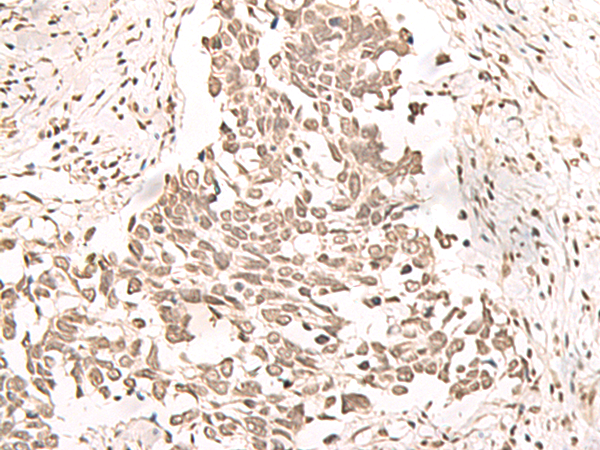

The image is immunohistochemistry of paraffin-embedded Human lung cancer tissue using (RRP1 Antibody) at dilution 1/40. (Original magnification: ×200)